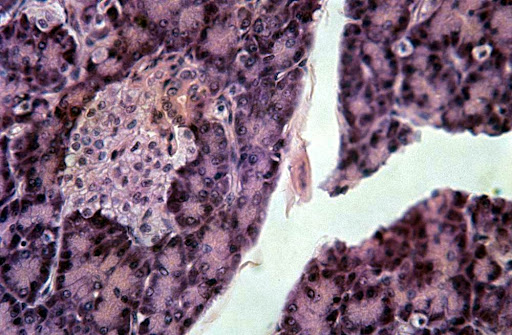

Images of Xeloda Pancreatic Cancer

Xeloda Pancreatic Cancer Pictures

Xeloda Pancreatic Cancer Images

Xeloda Pancreatic Cancer Photos

Photos of Xeloda Pancreatic Cancer

Pictures of Xeloda Pancreatic Cancer